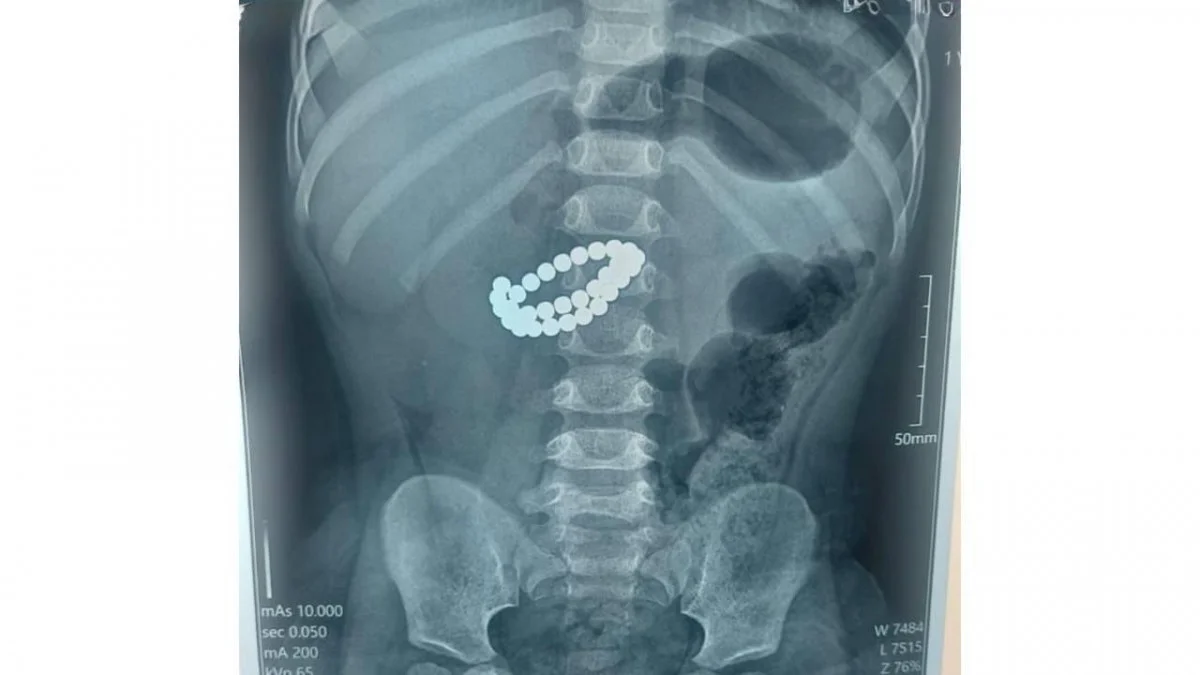

Алматыда 31 магнит жұтып қойған бір жасар балаға шұғыл ота жасалды

Алматыда хирургтер 31 магнит жұтып қойған баланың өмірін сақтап қалды.

Қоғамдық денсаулық сақтау басқармасының өкілдерінің хабарлауынша, Алматының Балаларға шұғыл медициналық көмек көрсету орталығында 31 магнит жұтып қойған сәбиге шұғыл ота жасалды.

Қабылдау бөліміне 1 жас 9 айлық бала өте ауыр жағдайда жеткізілген. Тексеру нәтижесінде дәрігерлер "ішектегі бөгде заттар – 31 магнит, жіңішке ішектің көп жерден тесілуі, перитонит" диагнозын қойды.

Баланың өмірін сақтап қалудың жалғыз жолы – шұғыл хирургиялық ота жасау еді. Дәрігерлер ортаңғы лапаротомия жасап, құрсақ қуысы ағзаларына толық тексеру жүргізді. Ота барысында магниттер ішектен алынып, жіңішке ішектегі көптеген тесік тігілді, құрсақ қуысы тазартылып, дренаж орнатылды. Сонымен қатар ішекке трансаналдық интубация жасалды, - делінген хабарламада.